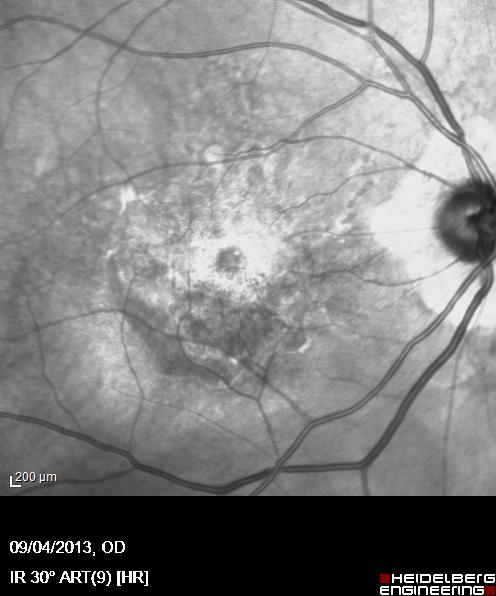

Oltre alle attività chirurgiche, il Dott. Acquaviva si avvale di tecnologie diagnostiche moderne per valutare in modo accurato lo stato di salute degli occhi. Esami come la tomografia a coerenza ottica (OCT), la pachimetria corneale e la misurazione del campo visivo sono strumenti fondamentali per un inquadramento completo e per la definizione del percorso terapeutico più efficace.